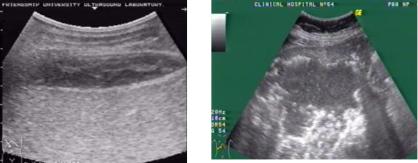

Уточнить диагноз поддиафрагмального или подпеченочного абсцесса позволяет ультразвуковое (рис. 86) и рентгенологическое исследование. Рентгенологическим признаком поддиафрагмального или подпеченочного абсцесса является наличие газового пузыря с горизонтальным уровнем жидкости, который изменяет свое направление при перемене положения тела больного.

Рис. 86. Ультратомограммы при поддиафрагмальном абсцессе справа (а) и подпеченочном абсцессе (б)